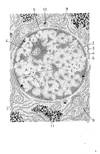

神経核;核Nucleus(Nucleus)

神経核;核【しんけいかく;かく】 Cluster of neurons outside of the cortex.(神経系ではある一つの機能にかかわる神経細胞の細胞体は集団を形成する傾向があり、この集団は末梢神経系では神経節、中枢神経系では神経核とよばれる。)